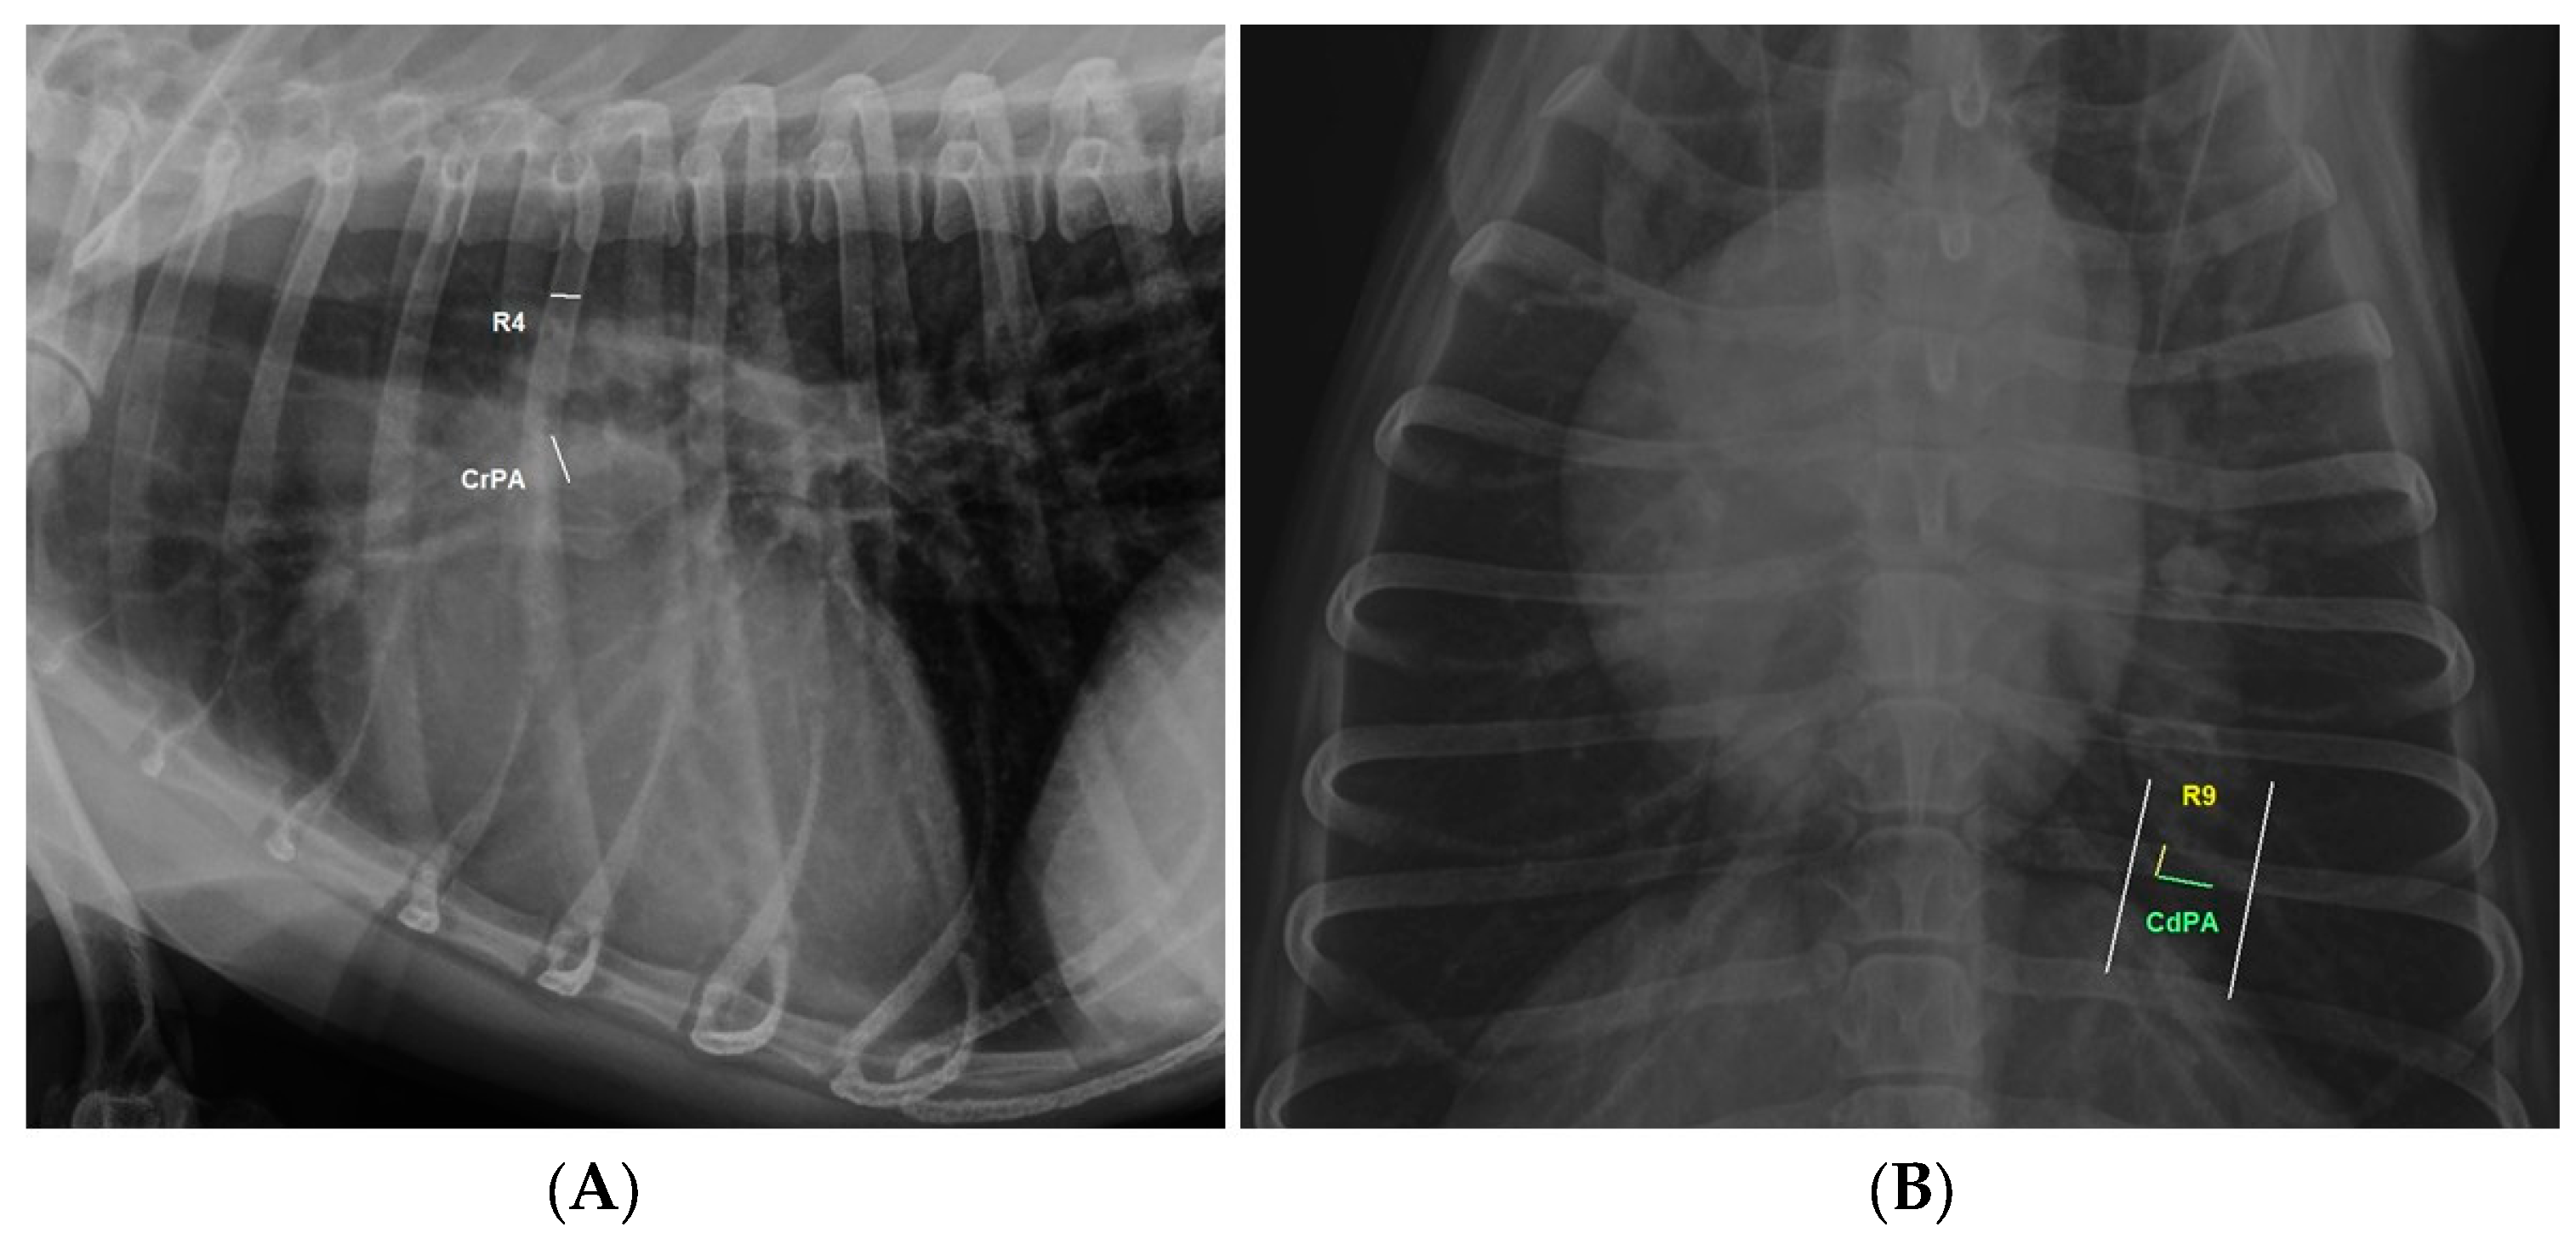

| IDAPD-CRPA/R4 | −0.4344274 *** | Moderate negative correlation |

| IDAPD-CDPA/R9 | −0.53781329 *** | Moderate negative correlation |

| CRPA/R4 | 0.959 | 0.77 | ≥1.08 | 87.5% | 70% |

| CDPA/R9 | 0.976 | 0.82 | ≥1.10 | 96.88% | 76.66% |

| CrPA/R4 | 4.31 | Large effect |

| CdPA/R9 | 0.702 | Moderate effect |